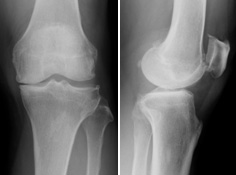

変形性膝関節症

膝関節の軟骨がすり減ることにより、関節炎や変形を生じ、痛みや可動域制限をきたす病気です。

中高年の女性に多く、国内で約1,000万人の患者がいると言われています。

主な症状としては、立ち上がる時や階段を降りる時の痛み、正座できなくなる・痛い、膝が腫れる・水がたまるなどの症状があります。

痛みが強く歩行障害がある場合は手術(関節鏡視下手術・骨切り術・人工膝関節置換術)が必要となります。